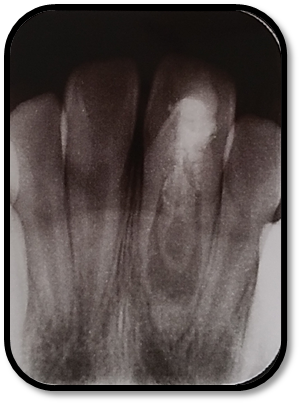

检查: 右上1牙冠略宽大,舌侧见粗大的畸形舌尖,叩痛(++),松Ⅰ°,唇侧牙龈红肿前庭沟膨隆扪痛,挤压唇侧龈缘溢脓,冷热测无反应,右侧上下1侧方颌,正中颌颌创伤。 X线:右上1发育7-8期,根管平行状,根尖孔宽大,约5-6mm宽,根尖周低密度影。髓腔根管宽大内见倒置牙影像,倒置牙可见髓腔。 余牙未见异常 6均已萌出建颌

随访复查: 治疗完成后1个月复查:右上1临床检查无阳性体征,叩痛(—),冷测无反应,无松动,牙龈无红肿,充填物完好,牙冠略有变色, X线检查:牙根根继续发育,可见钙化影像形成,如图示 治疗完成后7个月复查:临床检查无阳性体征,充填物完好,牙冠变色局部发黑,叩痛(—),冷测无反应,无松动,牙龈无红肿,临床及 X线检查:牙根继续发育,如图示 治疗完成后17个月复查:临床检查无阳性体征,充填物完好,牙冠变色局部发黑,叩痛(—),冷测无反应,无松动,牙龈无红肿。X线:牙根继续发育,根尖孔已近闭合。如图。 讨论: